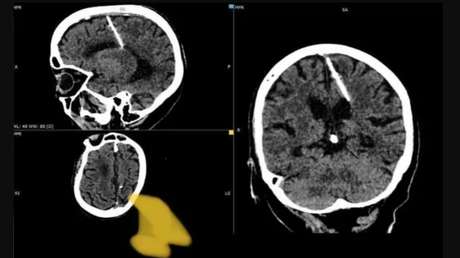

En la provincia rusa de Sajalín, unos radiólogos encontraron una aguja de 3 centímetros en el cerebro de una anciana de 80 años, informa el canal de Telegram del Ministerio de Sanidad de la región. Pese al tamaño del objeto y el lugar de incrustación, la mujer nunca experimentó ninguna incomodidad por su causa.

La mujer convive con el cuerpo extraño desde su nacimiento, ya que sus padres decidieron matarla clavándole la aguja durante la hambrienta en tiempos de la Segunda Guerra Mundial. En aquella época estos casos no eran infrecuentes: se introducía en la fontanela del bebé una fina aguja que dañaba el cerebro, causando la muerte y permitiendo ocultar la verdadera causa del fallecimiento.

Esta mujer tuvo suerte, ya que la aguja no solo no la mató, sino que tampoco le causó secuelas en forma de dolores de cabeza. Ahora la salud de la paciente no corre peligro y su estado está siendo vigilado por los médicos. Se decidió no realizar una intervención quirúrgica, ya que solo podría empeorar su estado.